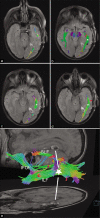

Figure 3:

Diffusion tensor imaging tractography 4 years after surgery, fused with initial 2D postoperative fluid-attenuated inversion recovery (FLAIR) magnetic resonance imaging (MRI) (syngo.via, Siemens, Munich, Germany). The ILF and inferior fronto-occipital fasciculus (IFOF) are part of the ventral stream and join posteriorly. The superior longitudinal fasciculus (SLF) represents the dorsal stream. (a-d): the reconstructed inferior longitudinal fasciculus (ILF) (white asterisk and green fibers) and posterior part of the IFOF, including their junction with the SLF (black asterisk and blue fibers), are depicted on craniocaudal axial FLAIR slices in relation to the temporobasal hypersignal. (e): 3D VRT reconstruction of the SLF, IFOF, and ILF in relation to the temporal FLAIR hypersignal (white star and lines, at the junction of the three tracts) on axial and sagittal images.